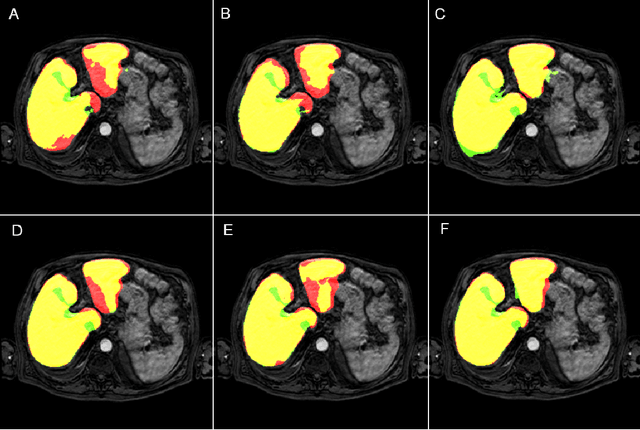

Abstract:Most MRI liver segmentation methods use a structural 3D scan as input, such as a T1 or T2 weighted scan. Segmentation performance may be improved by utilizing both structural and functional information, as contained in dynamic contrast enhanced (DCE) MR series. Dynamic information can be incorporated in a segmentation method based on convolutional neural networks in a number of ways. In this study, the optimal input configuration of DCE MR images for convolutional neural networks (CNNs) is studied. The performance of three different input configurations for CNNs is studied for a liver segmentation task. The three configurations are I) one phase image of the DCE-MR series as input image; II) the separate phases of the DCE-MR as input images; and III) the separate phases of the DCE-MR as channels of one input image. The three input configurations are fed into a dilated fully convolutional network and into a small U-net. The CNNs were trained using 19 annotated DCE-MR series and tested on another 19 annotated DCE-MR series. The performance of the three input configurations for both networks is evaluated against manual annotations. The results show that both neural networks perform better when the separate phases of the DCE-MR series are used as channels of an input image in comparison to one phase as input image or the separate phases as input images. No significant difference between the performances of the two network architectures was found for the separate phases as channels of an input image.